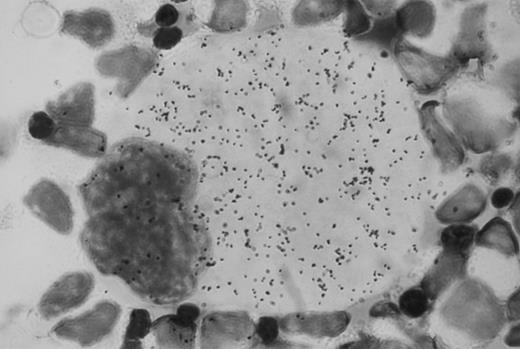

Autoradiographic analysis of 125I-Tpo binding to normal human bone marrow cells showed many grains associated with megakaryocytes (Fig 1). These grains were absent when the cells were incubated with 125I-Tpo in the presence of excess unlabeled Tpo. Grain counts showed that there were an average of approximately 1,300 grains per megakaryocyte in the presence of 125I-Tpo, and 200 grains per megakaryocyte in the presence of 125I-Tpo plus excess unlabeled Tpo. Thus, there were approximately 1,100 specifically bound grains per megakaryocyte. There was no detectable specific binding of 125I-Tpo to morphologically recognizable erythroblasts or myeloblasts. Parallel autoradiographic analysis of 125I-Tpo binding to the murine lymphoblastoid cell line BaF3 transfected with human Mpl receptor (BaF3-MplR cells) showed an average of 10 specifically bound grains per cell.

Autoradiographic analysis of 125I-Tpo binding to normal human bone marrow mononuclear cells. Original magnification × 100.

Autoradiographic analysis of 125I-Tpo binding to normal human marrow mononuclear cells and to BaF3-MplR cells was performed by incubating 125I-Tpo (0.6 nmol/L) with the cells in binding buffer for 1 hour at 37°C.39 The binding buffer consisted of RPMI 1640 (MA Bioproducts, Walkersville, MD) supplemented with 50 mmol/L HEPES (pH 7.4), 0.5% gelatin, 0.1% azide, and 10 μg/mL cytochalasin B. Parallel samples were incubated with 125I-Tpo plus a 100-fold excess of unlabeled Tpo. At the conclusion of the incubation, the cell suspension was gently layered on percoll (density, 1.028 g/mL) and centrifuged for 1 minute at 4°C in a Beckman Microfuge 11 (Beckman, Palo Alto, CA) to separate cell-associated 125I-Tpo from free 125I-Tpo. Cytopreparations were made using a Shandon Southern Cytospin (Shandon Co, Pittsburgh, PA). The samples were exposed to photographic emulsion for 3 weeks at 4°C and developed as previously described.39 43 Grain counts were performed on approximately 30 cells in each sample. Specific binding was defined as the number of grains overlaying the cells in the presence of 125I-Tpo minus the number of grains overlaying the cells in the presence of 125I-Tpo plus unlabeled Tpo.